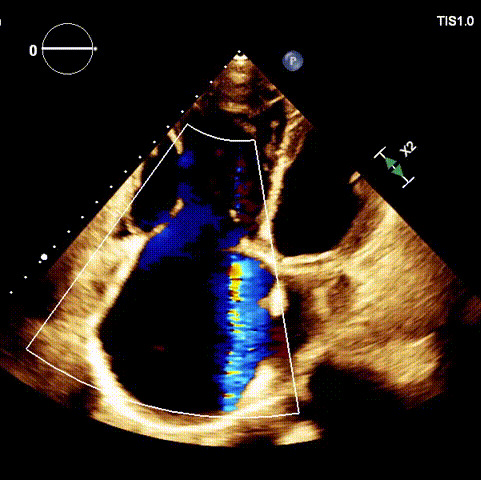

術前超聲心動圖及經(jīng)食道超聲提示

1.二尖瓣位機械瓣位置及功能未見異常;2.雙房及右室明顯擴大(左房收縮容積115ml,右房收縮容積370ml,右室中段左右徑65mm,右室FAC37%),下腔靜脈及冠狀靜脈竇擴張(下腔靜脈直徑44mm,冠狀靜脈竇直徑22mm);3.極重度三尖瓣反流(FTR 6+)。

術前超聲

術后超聲